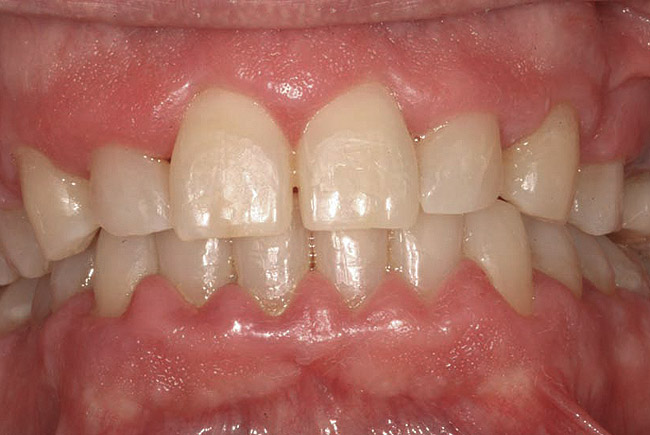

Drug-induced gingival enlargement is typically described as nodular, firm in consistency, and hard upon palpation. Clinical manifestations can be more severe in areas where local irritants such as plaque, defective restorations, and orthodontic or prosthetic appliances are present (Figure 1).7 Drug-induced gingival overgrowth is quite different between animals and humans. As demonstrated in rat models, the incidence of macroscopic gingival changes is usually close to 100% in all three of the previously mentioned classes of medication.8 In humans, however, the incidence has been reported to vary according to medication: 10% to 50% for phenytoin, 8% to 70% for cyclosporin-A, and 0.5% to 83% for nifedipine.6

Fig 1. A 66-year-old male patient with multiple restorations, taking 100 mg Dilantin (phenytoin) daily for approximately 5 years. (photo courtesy of Asim Alsuwaiyan, BDS)

Figure 1